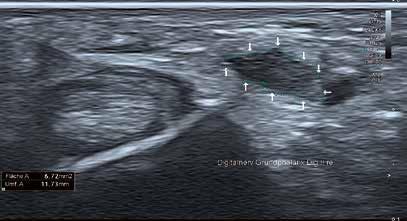

Wie kamen Sie zur Sonographie?

„Ultraschallsysteme am Bewegungsapparat und am Herzen haben mich die letzten 20 Jahre sehr intensiv begleitet. Ich habe 2001 meine herz- und gefäßchirurgische Facharztausbildung bei Prof. Haverich an der Med. Hochschule Hannover begonnen, wo ich bereits mit den Duplexverfahren die Carotiden und auch die Beinarterien prüfte. Eines meiner Forschungsprojekte war beginnend 2002 die Mikrozirkulation, die ich mit einem kombinierten Laser-Doppler- und Spektrophotometriesystem, dem Oxygento-see von LEA Medizintechnik, untersuchte – zunächst in der Herzchirurgie die Brustwanddurchblutung nach IMAEntnahme bei der Bypass-Operation und später die Handperfusion nach Radialisentnahme als arteriellem Graft.

Nach meinem Wechsel 2004 in die Unfallchirurgie habe ich z. B. mit einem portablen australischen Ultraschallsystem (USCOM) als Hubschraubernotarzt am Notfallort Hämodynamikmessungen mit Bestimmung des Herzzeitvolumens durchgeführt.

Das vorgenannte Oxygen-to-see-System habe ich dann an Achillessehnen eingesetzt und entdeckte 2005 einen gesteigerten Blutfluss bei midportion-Achillodynie, was im American Journal of Sports Medicine seinen Platz fand.“

Welche Systeme haben Sie begleitet?

„Für die klinische Sonographie am Bewegungsapparat habe ich in der MHH ein Toshiba System eingesetzt, bei dem ich einen hervorragenden Power-Doppler-Modus vorfand, um die Neogefäße an entzündeten Sehnen zu visualisieren. Ich habe 2005 begonnen, Power-Doppler-gesteuerte Sklerosierungen dieser Neogefäße mit Polidocanol vorzunehmen. Daher habe ich mich zu Beginn meiner Sportpraxis 2012 aufgrund der Power-Doppler-Sonographie für ein Toshiba Nemio System mit einem Linearschallkopf und einer Hockeysticksonde für die Handchirurgie entschieden. Dieses habe ich auch für die dynamische Sonographie von A1-Ringbandstenosen mit großem Gewinn eingesetzt.“

INTERVIEW // ULTRASCHALL // Aplio i800

Prof. Dr. Karsten Knobloch aus Hannover

56 // VISIONS 31

Warum haben Sie sich jetzt für ein Highend-Ultraschallsystem entschieden?

„2017 habe ich zum ersten Mal in einer Teststellung den weiterentwickelten Superb Micro Vascular Imaging (SMI) Modus getestet und war schon begeistert. Ich wollte aber zusätzlich eine verlässliche und einsetzbare quantitative Scherwellenelastographie, wie sie jetzt im Aplio i800 System zu finden ist. Außerdem sind die Matrixschallköpfe bis 33 MHz für mich von immenser Bedeutung.“

Wer sind Ihre Patienten in der Sportpraxis?

„Der typische Patient in meiner Sportpraxis ist männlich (in 70 % der Fälle), im mittleren Alter von 52 Jahren und stellt sich mit einem Achillessehnenproblem vor. Er ist Hobbyläufer oder Fußballer oder Tennisspieler und sucht mich häufig für eine Zweit-, Dritt- oder Viertmeinung zur gezielten Diagnostik und Therapie der Achillessehnenbeschwerden auf.“

Sie bieten in Ihrer Praxis Spitzendiagnostik für Sportler aus ganz Deutschland an. Was sind die häufigsten diagnostischen Fragestellungen für den Ultraschall?

„Für gewöhnlich suchen mich Patienten mit Sehnenproblemen auf, vornehmlich der Achillessehne, der Patellasehne, der plantaren Faszie am Fuß, aber auch weiterer Sehnen an der unteren Extremität wie der Quadricepssehne oder der Peronealsehnen. An der oberen Extremität sind die Supraspinatussehne und die lange Bizepssehne an der Schulter, die gemeinsame Extensorensehne am lateralen Ellenbogen, die Flexor-carpi-ulnaris-Sehne beim Golferellenbogen und die Handsehnen streck- wie beugeseitig schmerzhaft. Nach der eingehenden Anamnese und der klinischen Untersuchung inklusive Funktions- und z. T. Krafttests führe ich dann eine umfassende Ultraschalluntersuchung unter Einsatz der Graustufensonographie, der unterschiedlichen Dopplermethoden und neuerdings auch der Scherwellenelastographie durch.“

Welchen Stellenwert hat die Hochfrequenzsonographie in Ihrer Praxis?

„Bei jedem von mir sonographierten Patienten setze ich die Power-Doppler-Sonographie und den SMI-Modus zur präzisen Beurteilung der Mikrogefäßarchitektur ein. Die PowerDoppler-kontrollierte Injektionstherapie bei Tendinopathien –sei es mit Polidocanol zur Sklerosierungsinjektion oder der Hyaluronsäure Ostenil Tendon – ist eine ganz wesentliche Therapieoption für Tendinopathien an der oberen und unteren Extremität in meiner Sportpraxis.“

Beeinflusst die neue Technik Ihre therapeutische Vorgehensweise?

„Ja, durch das SMI in Ergänzung zur Power-Doppler-Sonographie kann ich noch präziser die Neovaskularisation visualisieren, wobei ich mir zunächst in SMI colour, dann auch im SMI-monochrome-Modus – ähnlich einer in-vivoMikroskopie – ein genaues Mikrogefäßbild mache.“

VISIONS 31 // 57 © 2021 C ANON MEDICAL SYSTEM S

„Bei jedem von mir sonographierten Patienten setze ich die Power-DopplerSonographie und den SMI-Modus zur präzisen Beurteilung der Mikrogefäßarchitektur ein.“

Welchen Nutzen haben Ihre Patienten davon?

„Je präziser und quantitativer die Diagnose, desto besser lässt sich einerseits der Schweregrad beispielsweise einer Achillodynie einschätzen und umso besser können prognostische Einschätzungen und therapeutische Empfehlungen gegeben werden.“

Wie bewerten Sie die neuen Möglichkeiten der quantitativen Beurteilung der Gewebeelastizität für den Bewegungsapparat?

„Für mich ist die quantitative Scherwellenelastographie, die es mir nichtinvasiv ermöglicht, eine Aussage über die Gewebehärte zu generieren, offen gesagt eine Offenbarung. Ich lerne mit jedem untersuchten Patienten die Elastizität der untersuchten Sehne in m/s besser kennen und beobachte auch den Einfluss meiner therapeutischen Bemühungen mit den unterschiedlichen von mir eingesetzten Techniken.“

Eröffnung der SPORTPRAXIS am 1. Dezember 2012. Im Bild: Prof. Knobloch mit Philipp Bargfrede, SV Werder Bremen. Kevin DeBruyne, derzeit Manchester City.

58 // VISIONS 31

Alex Meier, ehemals Eintracht Frankfurt, jetzt U16-Trainer Eintracht Frankfurt.

In puncto Bildgebung und Diagnostik sind Sie sehr innovativ unterwegs. Welche Entwicklungen wünschen Sie sich in naher Zukunft für den Ultraschall?

„Ich darf kurz ergänzen – auch in der Therapie bin ich sehr innovativ, setze nichtinvasive Techniken wie die fokussierte und radiale Stoßwellentherapie, die Low Level Lasertherapie, neuerdings auch die ultraschallgestützte galvanische Elektrolyse (Gymna Acure 8000) wie auch die extrakorporale Magnetotransduktion (EMTT) mit dem Magnetolithsystem ein. Von der Sonographie erhoffe ich mir in der Zukunft u. a. eine Fusion mit Schichtbildverfahren, insbesondere mit der Cone Beam CT, die ich als DVT in meiner Praxis für die Knochenbildgebung einsetze. Des Weiteren erhoffe ich mir weitere Verbesserungen in der Scherwellenelastographie oberflächennah <1 cm, wo mitunter Grenzen in der Erfassung der Scherwelle auftauchen. //

Spindelförmig verdickte midportion Achillestendinopathie auf 10,6 mm ap-Durchmesser vs. 6,8 mm auf der gesunden Gegenseite. Die Scherwellenelastographie zeigt die pathologische Elastizität mit 7,2 m/s (links) vs. 3,8 m/s (rechts).

„Für mich ist die quantitative Scherwellenelastographie, die es mir nichtinvasiv ermöglicht, eine Aussage über die Gewebehärte zu generieren, offen gesagt eine Offenbarung."

Prof. Dr. Karsten Knobloch, FACS

Prof. Knobloch 2005 als Notarzt im RTH Christoph 4 bei portabler Hämodynamikmessung mit dem USCOM-System.

M.

Osgood Schlatter, dargestellt mit SMI und Scherwellenelastographie. Nachweis der reduzierten Elastizität der distalen Patellasehne an der noch nicht vollständig verknöcherten Tuberositas tibiae.

VISIONS 31 // 59 © 2021 C ANON MEDICAL SYSTEM S

Ellenbogen eines Golfpatienten nach dreimonatiger Schmerzdauer. Darstellung der entzündeten M. flexor carpi ulnaris Sehne mit SMI. Die Sehne zeigt eine normale Elastizität.

Ein Plädoyer für hochwertige Ultraschallausrüstung in der neurologischen Praxis

Wenn Sie als Neurologe Besuch von Profi-Handwerkern bekommen, sind Sie in der Regel beeindruckt von deren Geräteausstattung mit meist High-End-Geräten namhafter deutscher oder Schweizer Hersteller.

Dagegen mutet ein Blick auf die Ultraschallausstattung in der eigenen Praxis oft ernüchternd an. Warum sind hier viele Kollegen so „sparsam“ unterwegs und ist das wirklich sinnvoll?

Bislang bestand die Anwendung des Ultraschalls in der neurologischen Praxis ausschließlich im vaskulären Ultraschall der hirnversorgenden Gefäße (also v. a. extra-/intrakranielle Doppler- und Duplexsonographie). Mit der Nerven- und Muskelsonographie hat sich in den letzten Jahren jedoch eine weitere Anwendungsmöglichkeit erschlossen, die insbesondere auch die Anschaffung qualitativ höherwertiger Geräte sinnvoll bzw. sogar nötig macht. Abgesehen davon, dass sich mit einer höherwertigen technischen Ausstattung natürlich auch bessere Befunde und damit für den Patienten bessere und ggf. wichtige diagnostische und therapeutische Entscheidungen treffen lassen, sprechen auch wirtschaftliche Aspekte eigentlich klar für den Einsatz von Premium-Ultraschallsystemen.

Beispiel für den vaskulären Ultraschall

Extrakraniell lässt sich in der Regel auch mit älteren und einfacheren Geräten zumindest die Carotisbifurkation zuverlässig darstellen. Schwieriger sind oftmals bereits die distalen Abschnitte der A. carotis oder die A. vertebralis (inkl. deren Abgängen) darstellbar, was zudem durch ungünstige anatomische Verhältnisse/eine ungünstige anatomische Konstitution des Patienten nochmals erschwert werden kann. Intrakraniell ist mit älteren oder einfacheren Geräten häufig kein adäquates Schallfenster zu finden oder sind die intrakraniellen Gefäße nur schwierig und im Rahmen einer langwierigen Suche unter Optimierung des dürftigen Schallfensters darstellbar. Teilweise ist auch gar keine Untersuchung möglich, die mit leistungsstärkeren Geräten ggf. doch noch gelingen würde.

Aufgrund eigener Erfahrungen/Versuche mit unterschiedlichen Geräteklassen ist eine Zeiteinsparung pro Untersuchung von mind. 1 min bei Verwendung höherwertiger Geräte absolut realistisch. Bei konservativer Annahme von 150 Untersuchungen pro Quartal würde sich somit eine jährliche Zeitersparnis von ca. 10 h ergeben. Bei einem Umsatz/Stunde von 200 bis 300 € wäre dies eine Ersparnis von mind. 2.000 €.

Unser Gespräch mit Dr. Axel Schramm aus der neurologischen Gemeinschaftspraxis in Fürth. Dr. Axel Schramm

INTERVIEW // ULTRASCHALL // NeuroPraxis Fürth 60 // VISIONS 31

Circulus arteriosus inkl. sehr guter Sicht auf den Hirnstamm. A. und V. vertebralis.

seits ist eine Untersuchung bei Standardanwendungen wie dem Karpaltunnel- und Sulcus-Ulnaris-Syndrom (inkl. Auswertung der Nervenquerschnittsfläche in 2 Ebenen) mit entsprechender technischer Ausstattung mit 1–2 min sehr schnell durchführbar! Bei Privatpatienten lassen sich in ca. 2–3 min z. B. der N. medianus und die Medianus-versorgte Thenarmuskulatur darstellen, was sich mit den Ziffern 1x 410 und 3x 420 (Nervensonographie rechts, links; Muskelsonographie rechts, links) abbilden lässt.

Dies generiert bei 2,3-fachem bzw. aufgrund der Verwendung spezieller hochauflösender Ultraschallsonden ggf. zu rechtfertigendem 3,5-fachem Steigerungssatz Einnahmen von 58,97 € (410 = 26,81 € + 3x 420 = 32,16 €) bzw. 89,76 € (410 = 40,80 € + 3x 420 = 48,96 €). Bei der Anwendung des NMUS lassen sich also bereits bei 1–2 Privatpatienten im Monat lukrative Zusatzeinnahmen generieren.

Beispiel

den Nerven- und Muskelultraschall (NMUS)

Die Etablierung einer neuen Ultraschallanwendung, wie z. B. des Nerven- und Muskelultraschalls, in der Praxis führt natürlich zunächst immer auch zu einer besseren Geräteauslastung und damit zur Reduktion von Anschaffungs- und laufenden Kosten.

Allerdings ist die Vergütung insbesondere bei Kassenpatienten mit ca. 6,15 € (Ziffer 33081 ohne Zertifizierung durch die KV) bzw. 7,91 € (Ziffer 33100 mit Zertifizierung durch die KV) eher gering. Anderer-

„Eine jährliche Zeiteinsparung im vaskulären Bereich von mind. 10 h bei Verwendung höherwertiger Geräte ist absolut realistisch!“

für

N. medianus am Unterarm und vor dem Karpaltunnel bei CTS.

VISIONS 31 // 61 © 2021 CANON MEDICAL SYSTEMS

Dr. Axel Schramm.

Der wirtschaftliche Benefit der Methode liegt aber nur zum Teil in der Möglichkeit, weitere Leistungen abzurechnen. Mit der Methode lassen sich insbesondere neurophysiologische Untersuchungen einsparen (z. B. schneller Ausschluss eines sowieso unwahrscheinlichen Karpaltunnelsyndroms) oder gezielter und damit effektiver einsetzen (z. B. Vorselektion von Muskeln für eine in der Regel aufwändige EMG-Untersuchung).

Konservative Gesamtrechnung für den Nerven- undMuskelultraschall

Nervenläsionen bzw. -verletzungen detektieren und damit zuverlässige Entscheidungen hinsichtlich der weiteren, ggf. operativen Therapie treffen.

Last, but not least ist zudem hinzuzufügen, dass die Verwendung technisch höherwertiger Geräte auch mit einem erheblichen Zugewinn an Spaß und Erleichterung bei der Arbeit verbunden ist –und das gilt nicht nur für Handwerkergeräte namhafter deutscher/ Schweizer Hersteller, sondern insbesondere auch für den Ultraschall in der neurologischen Praxis.

Vielen Dank für das Gespräch! // 1–2 Privatpatienten im Monat ergeben einen Umsatz von ca. 1.000 € im Jahr.

Die kassenärztlichen Leistungen über die Ziffern 33081 und 33100 generieren lediglich ca. 25 € pro Woche und ergeben einen Jahresumsatz von ca. 1.000 €.

Durch Einsparung von neurophysiologischen Untersuchungen im Umfang von ca. 10 Arbeitsminuten pro Woche (entsprechend 400 min oder 6,5 h/Jahr) sind das bei einem Stundensatz von 200 €/h etwa 1.300 € Einsparungen im Jahr.

In der Summe ergeben sich für den Nerven- und Muskelultraschall etwa 3.000 € Einnahmen im Jahr.

Für beide Anwendungsbereiche zusammen ergeben sich bei sehr konservativer Rechnung realistische Einsparungen und Zusatzerlöse von gut 5.000 € im Jahr. Legt man eine Gerätelaufzeit von 8 Jahren zugrunde, so lassen sich bei der Anschaffung eines neuen Ultraschallgeräts Mehrinvestitionskosten von bis zu 40.000 € rechtfertigen.

Diese Modellrechnungen sollen dabei jedoch kein Aufruf zur Gewinnoptimierung sein, sondern lediglich zeigen, dass Investitionen in eine verbesserte Ultraschallausrüstung und Diagnostik sich wirtschaftlich zumindest amortisieren.

Hinzu kommt wie gesagt – und für uns als Ärzte natürlich letztlich am wichtigsten –, dass eine verbesserte Diagnostik in erster Linie dem Patienten zugute kommt. Im vaskulären Bereich bezieht sich das insbesondere auf eine optimierte Detektion und Graduierung von Gefäßstenosen sowie eine verbesserte Risikoeinschätzung und Beratung hinsichtlich der weiteren Therapie. Im Bereich Nerven- und Muskelultraschall lassen sich durch die hochauflösende Sonographie insbesondere auch kleine und komplexe

Dr. Axel Schramm ist seit Mitte 2016 in eigener neurologischer Gemeinschaftspraxis in Fürth tätig.

Als langjähriger Oberarzt und Leiter des Neurophysiologischen Labors der Neurologischen Universitätsklinik Erlangen hat er die Nervenund Muskelsonographie (NMUS) dort etabliert und sich auch wissenschaftlich mit dem Thema befasst.

Als Seminarleiter für Nerven- und Muskelsonographie der Dt. Gesellschaft für Ultraschall in der Medizin (DEGUM) hält er regelmäßig Vorträge und Kurse zum Thema NMUS und ist an der Fortentwicklung der Methode inkl. der federführenden Etablierung von 3D-Verfahren interessiert. Der klinische Schwerpunkt in der eigenen Praxis liegt u. a. in der neurosonologischen Diagnostik (vaskulär, NMUS) sowie insbesondere in Kombination mit der Neurophysiologie.

„Mit der Hochfrequenzsonographie lassen sich insbesondere neurophysiologische Untersuchungen einsparen oder gezielter und effektiver einsetzen.“

62 // VISIONS 31

Veranstaltungen & Workshops 2021/22

2021

21.08. Berlin

BNK Niederlassungsseminar

28.08. Hannover

Niedersächsischer Gynäkologentag

02. – 04.09. Münster

61. DGH-Kongress

03. – 04.09. Leipzig

3. Anwenderseminar Muskel- und Nervensonographie

15. – 18.09. Stuttgart

73. Kongress der Deutschen Gesellschaft für Urologie

13. – 18.09. Leipzig

Viszeralmedizin 2021

17. – 18.09. Würzburg

CEUS in Dresden IX

30.09. – 02.10. Landshut/Essenbach

73. Jahrestagung und MTRA-Tagung der Bayerischen Röntgengesellschaft 2021

03.10. Hofheim, Digital

22. Hofheimer Tierärztetag und 8. Tagung für Tiermedizinische Fachangestellte

06. – 08.10. Digital

56. Jahrestagung der Deutschen Gesellschaft

für Neuroradiologie e.V. (neuroRAD 2021)

06. – 09.10. Berlin, Hybrid

Kongress für Kinder- und Jugendmedizin 2021 (DGKJ)

22. – 23.10. Hamburg

Uro-Andrologisches Symposium –Meet the Experts

27. – 29.10. Wien

Ultraschall 2021 (DLT)

03.11. Stuttgart

Canon SONOSALES

04. – 05.11. Dortmund

13. RadiologieKongressRuhr

04. – 06.11. Rostock-Warnemünde

Ultraschall in Warnemünde 2021

06.11. München

10.11. Frankfurt

12.11. Neuss

13.11. Chemnitz

9. Mitteldeutsche Tagung Neonatologie und Pädiatrische Intensivmedizin (MITANPI)

18. – 20.11. Berlin

DVG-Vet-Congress 2021

20.11. Rheine

12. Rheiner Symposium für Gynäkologie und Perinatalmedizin

20.11. Essen

27.11. Hamburg

04.12. Dresden

09. – 11.12. Berlin, Hybrid EuroEcho 2021

2022

14. – 15.01. Köln

Update RSNA

22.01. Dortmund

DEGUM Refresher-Kurs Dopplersonographie

11. – 12.02. Hamburg

04. – 05.02.

Radiologiekongress Nord

Baden-Baden

Frühjahrskurse der VSRN

27. – 26.06. Wiesbaden, Hybrid

103. Deutscher Röntgenkongress

Immer aktuell – online unter: https://de.medical.canon/events/

Präsenz Hybrid Digital

Termine // CT, MR, Röntgen und Ultraschall // 2021/22

DATUM ORT/VERANSTALTUNG DATUM ORT/VERANSTALTUNG

VISIONS 31 // 63 © 2021 C ANON MEDICAL SYSTEM S

Gelenkerkrankungen im Kindesalter

Privatdozent Dr. Daniel Windschall leitet die Klinik für Kinder- und Jugendrheumatologie im Rheumatologischen Kompetenzzentrum Nordwestdeutschland im St. Josef-Stift in Sendenhorst bei Münster, eine von zwei deutschen Spezialkliniken für kindliches Rheuma. Im Interview spricht er darüber, welchen diagnostischen Nutzen seine Abteilung durch den Einsatz des Highend-Ultraschallsystems Aplio i800 für Diagnostik, Therapie und Monitoring erfährt.